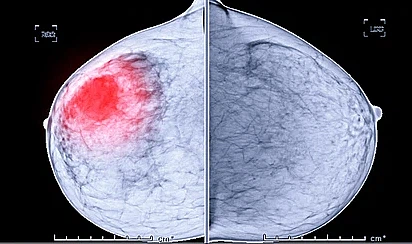

유방암 초기 증상 1. 응어리가 만져지는 경우

유방암 초기 증상으로 응어리나 멍울이 만져지면 유방암 초기 증상을 의심해보아야 합니다. 가슴이나 겨드랑이 방향을 손으로 만졌을 경우 울퉁불퉁한 혹이 느껴진다면 의심해 보아야 합니다. 악성 종양인 경우 일반적으로 단단하고 고정되어 이동하지 않고 모양이 불규칙합니다. 하지만 멍울은 유선 내에 있는 혹으로, 90%가 양성 진단을 받는 것으로 알려져 있습니다. 이러한 응어리 멍울은 유방암과 관계없는 섬유선종이나 섬유낭종일 가능성도 높아 의료기관에서 정확히 진찰받는 것이 좋습니다.

유방암 치료 - 외과수술

암세포 조직을 없애는 시술을 합니다. 조직 적출 시술 중 림프절을 같이 제거하여 림프절 전이를 확인합니다. 전이가 없으면 림프절 절제술을 중지하고 전이가 있으면 액와 림프절을 추가로 제거합니다. 시술 전에 이미 림프 절으로의 전이가 확인된 경우에는 추가 절제술이 가능할 수 있습니다. 암세포의 위치와 사이즈에 따라서 유방조직을 살릴 수 있고 향후 재건수술도 고려해볼 수 있습니다. 최근에는 의학기술이 발달하면서 최대한 보존하려는 경향이 있지만, 암세포의 사이즈가 크거나 전이되면 어쩔 수 없이 많은 부분을 절제하게 됩니다.

현재 국내 유방암 환자의 약 90퍼센트가 방사선 치유를 받고 있습니다. 약 50년 전까지만 해도 대부분의 유방암의 표준 치료방법이 유방암 절제였겠습니다만 요즘에는 초중기 유방암이 거의 유방 보전 시술로 발전되고 있습니다. 유방 보전 시술을 할 경우 재발률은 약 30퍼센트 수준이고 방사선 치료를 추가한다면 재발률을 약 70퍼센트 줄일 수 있어 유방 절제술과 비슷한 치유 결과를 얻을 수 있습니다.